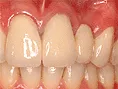

| 自費ブリッジ |

通常のブリッジでは 正面から金属が見えてしまいますが ピンレッジでは見えません ■長所 ・金属が見えない ■短所 ・前後の歯を裏だけ削る ・前後の歯が健全な場合のみ可能 ・高い |